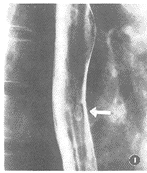

Behcet病的食管损害首次报道于1971年,迄今世界仅有数10例报道[3,4]。食管各段均可受累,但以中下段多见,食管溃疡、狭窄及穿孔为主要病变。其X线表现为龛影,本组9例病人中共有15个龛影,龛影可以单发或多发,形态多样,呈类圆形、椭圆形、纵形和不规则形,本组半数以上(67%)龛影为类圆形和椭圆形,龛影边界清楚,周边可见环状透亮晕(图1),与肠型Behcet病的末端回肠环形溃疡的表现非常类似[5]。纵行或不规则龛影,有时与食管癌及Crohn病不易区别,但龛影较大,却无充盈缺损,管壁柔软无破坏。食管Behcet病的溃疡大小不等,单发者龛影较大,多发者龛影大小不等,89%龛影大于1 cm。溃疡深浅不一,如果溃疡较浅,X线不容易发现,应在食管低张,大量充气使食管扩张的情况下,大口吞钡,在钡剂流动的过程中,显示浅龛影,另外应注意腔壁线的连续性和完整性。如果溃疡反复发作,可造成食管狭窄,狭窄的范围及程度与病变累及的范围及病史长短有关,一般狭窄两端与正常食管无明确分界,与正常食管逐渐移行(图2),据此可与食管癌进行鉴别。如果溃疡深达浆膜层造成穿孔,可形成食管气管瘘,或穿入纵隔,食管穿孔是食管 Behcet病人的主要死亡原因。总之,食管Behcet病非常少见,并且诊断困难,如果X线检查发现食管中下段较大的龛影,类圆形或椭圆形,边界清楚,周围有环状透亮晕,或伴有无明确分界的食管狭窄,临床有原因不明的反复发作的口腔或生殖器溃疡者,应考虑到食管Behcet病的可能,应进行反复多次内镜活检,病理检查有小血管炎为相对特征性改变。

图1 食管Behcet病。食管椭圆形龛影,边界清楚,周边可见环状透亮晕 图2 食管Behcet病。食管轻度狭窄,粘膜表面不平,见多发类圆形、椭圆形及不规则龛影,有粘膜皱襞集中及皱襞增宽,狭窄两端与正常食管逐渐移行■